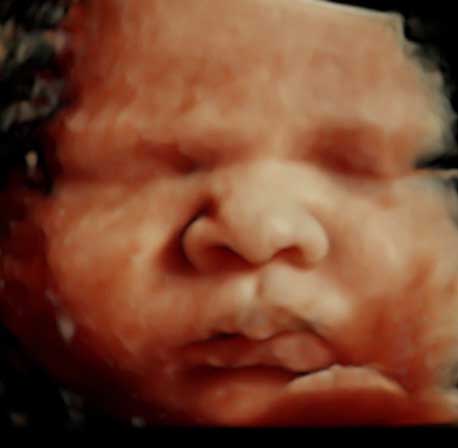

3D/4D Gender Reveal - Starting at 13 Weeks - $65

5-10 minute 3D/4D ultrasound session

10-15 minute 3D/4D/HD live ultrasound session

Surprise 3d/4d/5d - $99

This session is a 10-15 minutes 3D/4D/HD Live ultrasound.